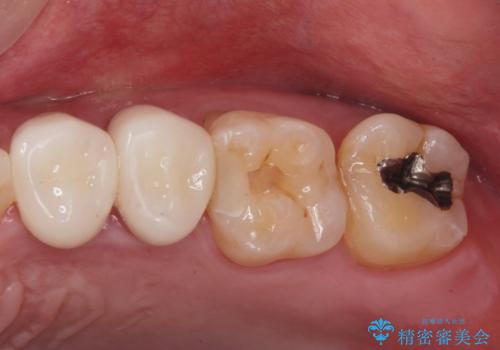

銀が目立つので白くしたい

担当医 青山卓弘